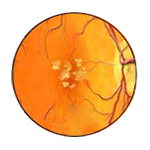

Ocular Histoplasmosis Syndrome

Caused by a fungus commonly found in certain dust and soil.